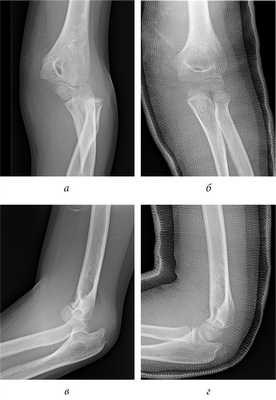

После утверждения протокола исследования местным этическим комитетом из базы данных детской больницы Salesi были отобраны записи всех пациентов, которые в период с 1 января 2014 г. по 31 декабря 2017 г. обращались в отделение неотложной помощи по поводу ПМН. Хирург-ортопед проводил классификацию ПМН по Watson-Jones (WJ) [9] и Papavasiliou [10]. Критериями включения в данное исследование были ПМН с внутрисуставным ущемлением в локтевом суставе, изолированные ПМН (III тип по WJ) или ПМН с вывихом предплечья (IV тип по WJ). В исследование включено 13 детей (5 мальчиков и 8 девочек), средний возраст которых составил 10,9 года (8-13 лет). Согласно записям в исследование было включено 6 пациентов с изолированным ПМН с внутрисуставным ущемлением в локтевом суставе (III тип по WJ) и 7 пациентов с ПМН с внутрисуставным ущемлением в локтевом суставе после закрытой репозиции по поводу сопутствующего заднелатерального вывиха предплечья (IV тип по WJ) (рис. 1). У 6 пациентов до операции наблюдалась парестезия в зоне иннервации локтевого нерва. В отделении неотложной помощи была выполнена рентгенография локтевого сустава в стандартных переднезадней и боковой проекциях. Для подтверждения внутрисуставного ущемления до операции одному пациенту была проведена трехмерная компьютерная томография (рис. 2). Перед исследованием было получено информированное согласие родителей/опекунов пациентов на использование медицинских карт их детей. Среднее время наблюдения составило 24,1 мес. (11-44 мес.).

Рис. 1. Пациент С. Вывих предплечья с внутрисуставным ущемлением медиального надмыщелка: а, б — рентгенограмма вывиха предплечья; в, г — рентгенограмма после устранения вывиха предплечья с внутрисуставным ущемлением медиального надмыщелка